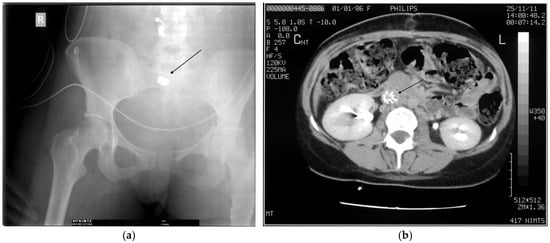

- Serafetinides, E.S. Renal and ureteric trauma. In Primer on Urology; Chapple, C.R., Wein, A.J., Eds.; Springer: Cham, Switzerland, 2025; pp. 1013–1024. [Google Scholar] [CrossRef]

- Karademir, K.; Gunhan, M.; Can, C. Effects of blast injury on kidneys in abdominal gunshot wounds. Urology 2006, 68, 1160–1163. [Google Scholar] [CrossRef]